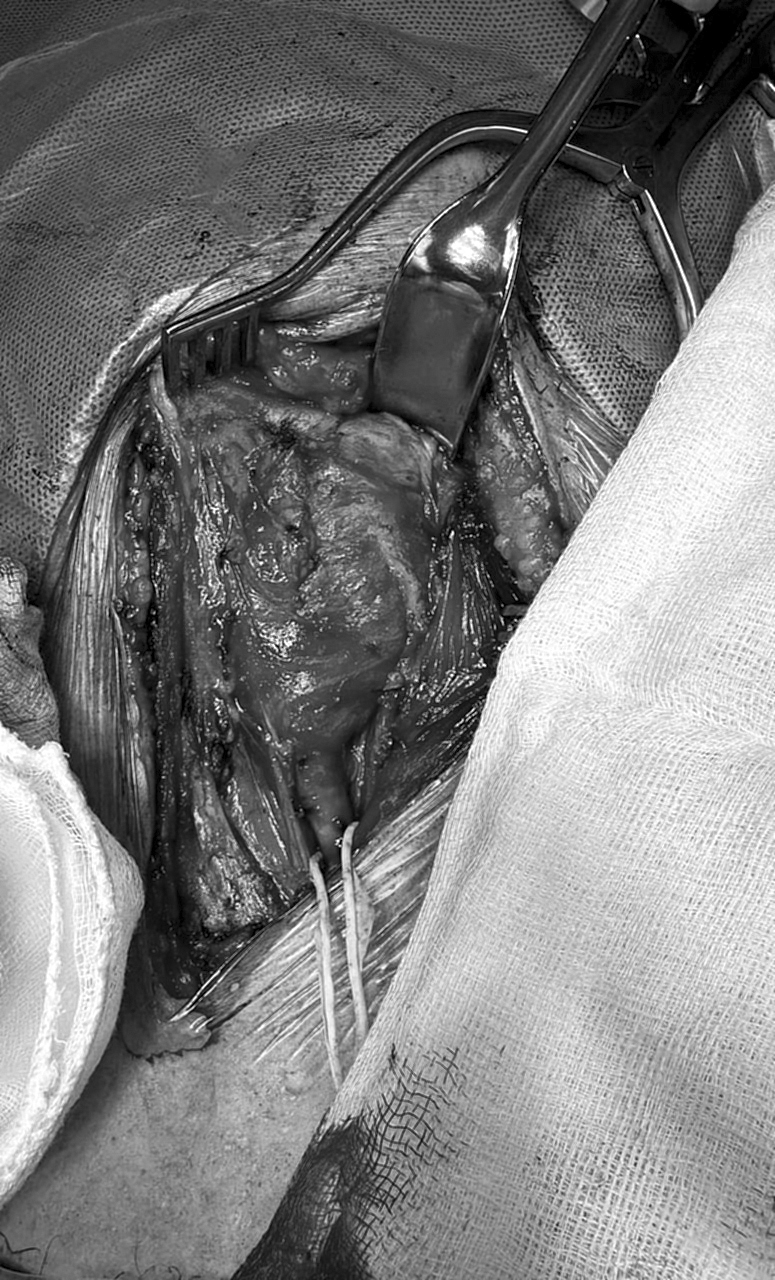

“Por lo tanto ante esta circunstancia de la probabilidad de sangrado, durante la cirugía se realizó colecta de su propia sangre. Es decir un procedimiento denominado autotransfusión, mediante la labor del Banco de Sangre del Hospital Central”.

La exéresis (extirpación quirúrgica) se realizó con éxito.

“El paciente fue sometido a cirugía con éxito con extirpación total del tumor. El mismo recibió su propia sangre como transfusión y fue dado de alta llegado el séptimo día post-operativo sin ningún déficit ni complicaciones” explicó el Dr. Filizzola.